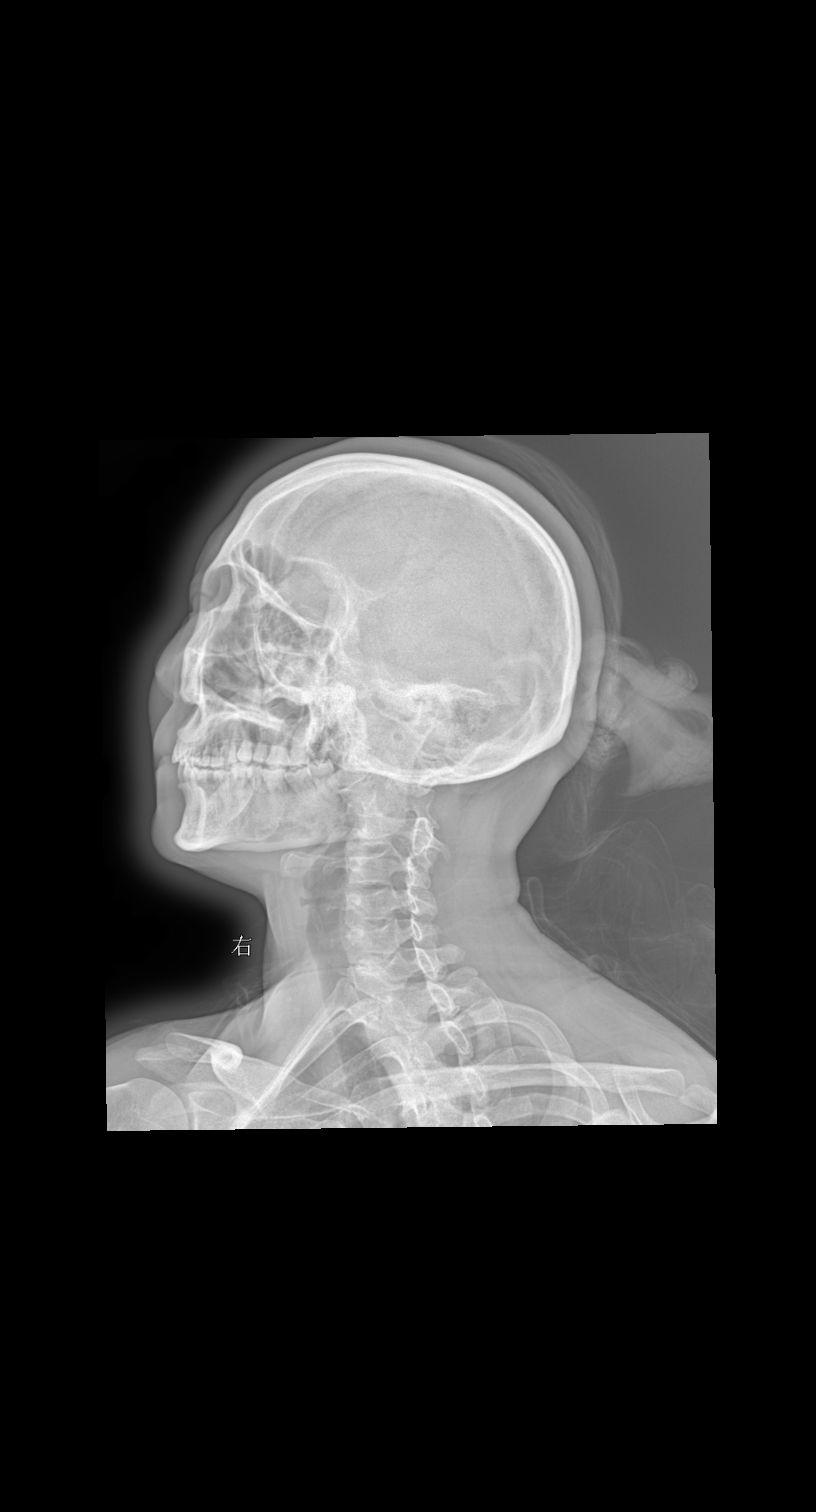

来张颈椎四位片瞅瞅大家怎么拍的